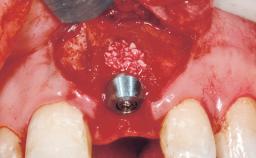

| Placement Protocol | Immediate implant placement |

| Socket Morphology | Single-root socket |

| Socket Integrity | Sufficient, with intact bone walls |

| Bone Volume | Sufficient, with intact walls |